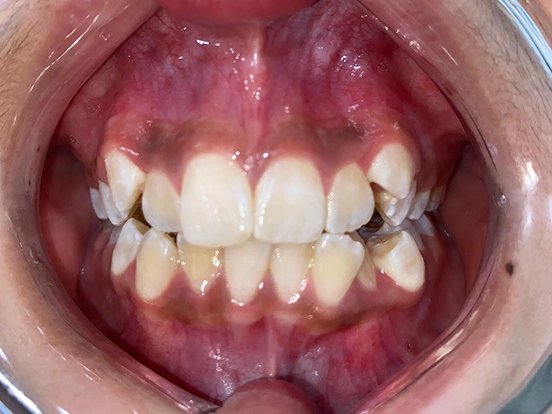

Braces EJ

EJ’s braces journey demonstrates how traditional orthodontics can deliver a complete and lasting smile transformation. The braces effectively corrected spacing and bite issues, leaving behind a perfectly straight, radiant smile that reflects months of dedication.